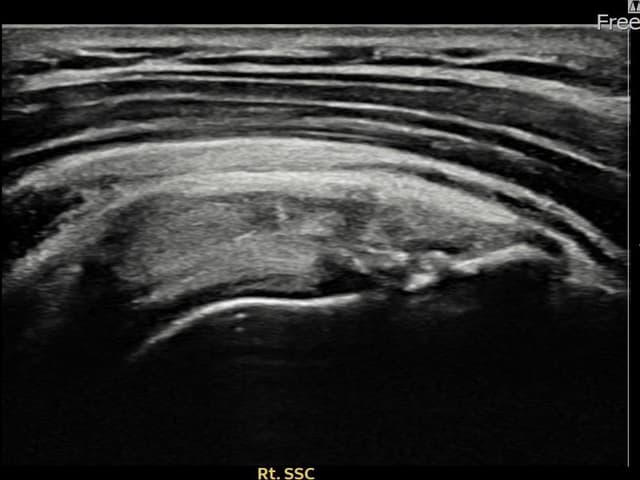

右侧 견갑하근건 部分撕裂

8mm × 3mm (肌腱厚度约32%缺损)